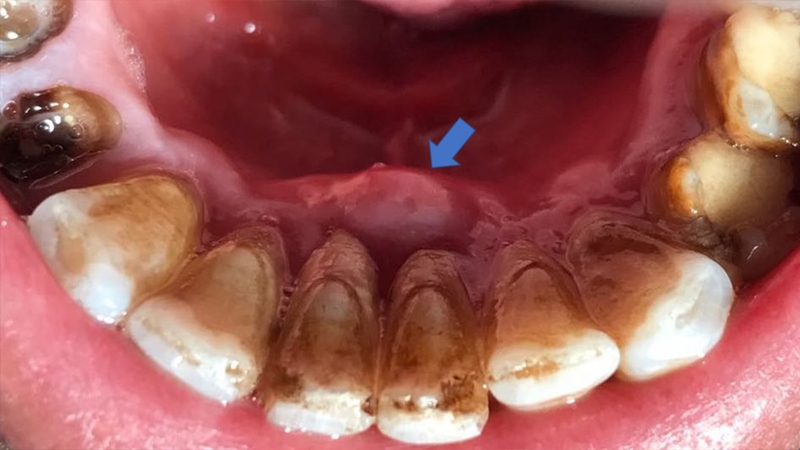

Lấy tủy răng là một biện pháp điều trị cho bệnh nhân viêm tủy răng không thể hồi phục. Viêm tủy răng diễn biến nặng hơn sẽ làm bệnh nhân rất đau đớn đặc biệt là vào ban đêm, hơi thở có mùi hôi và khó khăn trong việc ăn uống. Do đó, viêm tủy răng ảnh hưởng xấu đến sinh hoạt hằng ngày và sức khỏe của người bệnh.

Bên cạnh đó, viêm tủy răng còn có thể dẫn đến các biến chứng nguy hiểm như áp xe ổ chân răng, lây lan sang các răng khác, làm mất răng và nhiễm trùng máu. Vì vậy, bệnh nhân viêm tủy răng nặng cần được lấy tủy răng càng sớm càng tốt.

Tuy nhiên, răng hàm và răng bị nhiễm khuẩn sẽ phải lấy tủy răng từ 2 lần trở lên. Bởi vì răng hàm có nhiều ống tủy trong chân răng nên không thể lấy xong chỉ trong một lần. Đối với răng bị viêm nhiễm, các bác sĩ sẽ phải khử khuẩn trước thì mới thực hiện hoàn tất quy trình.